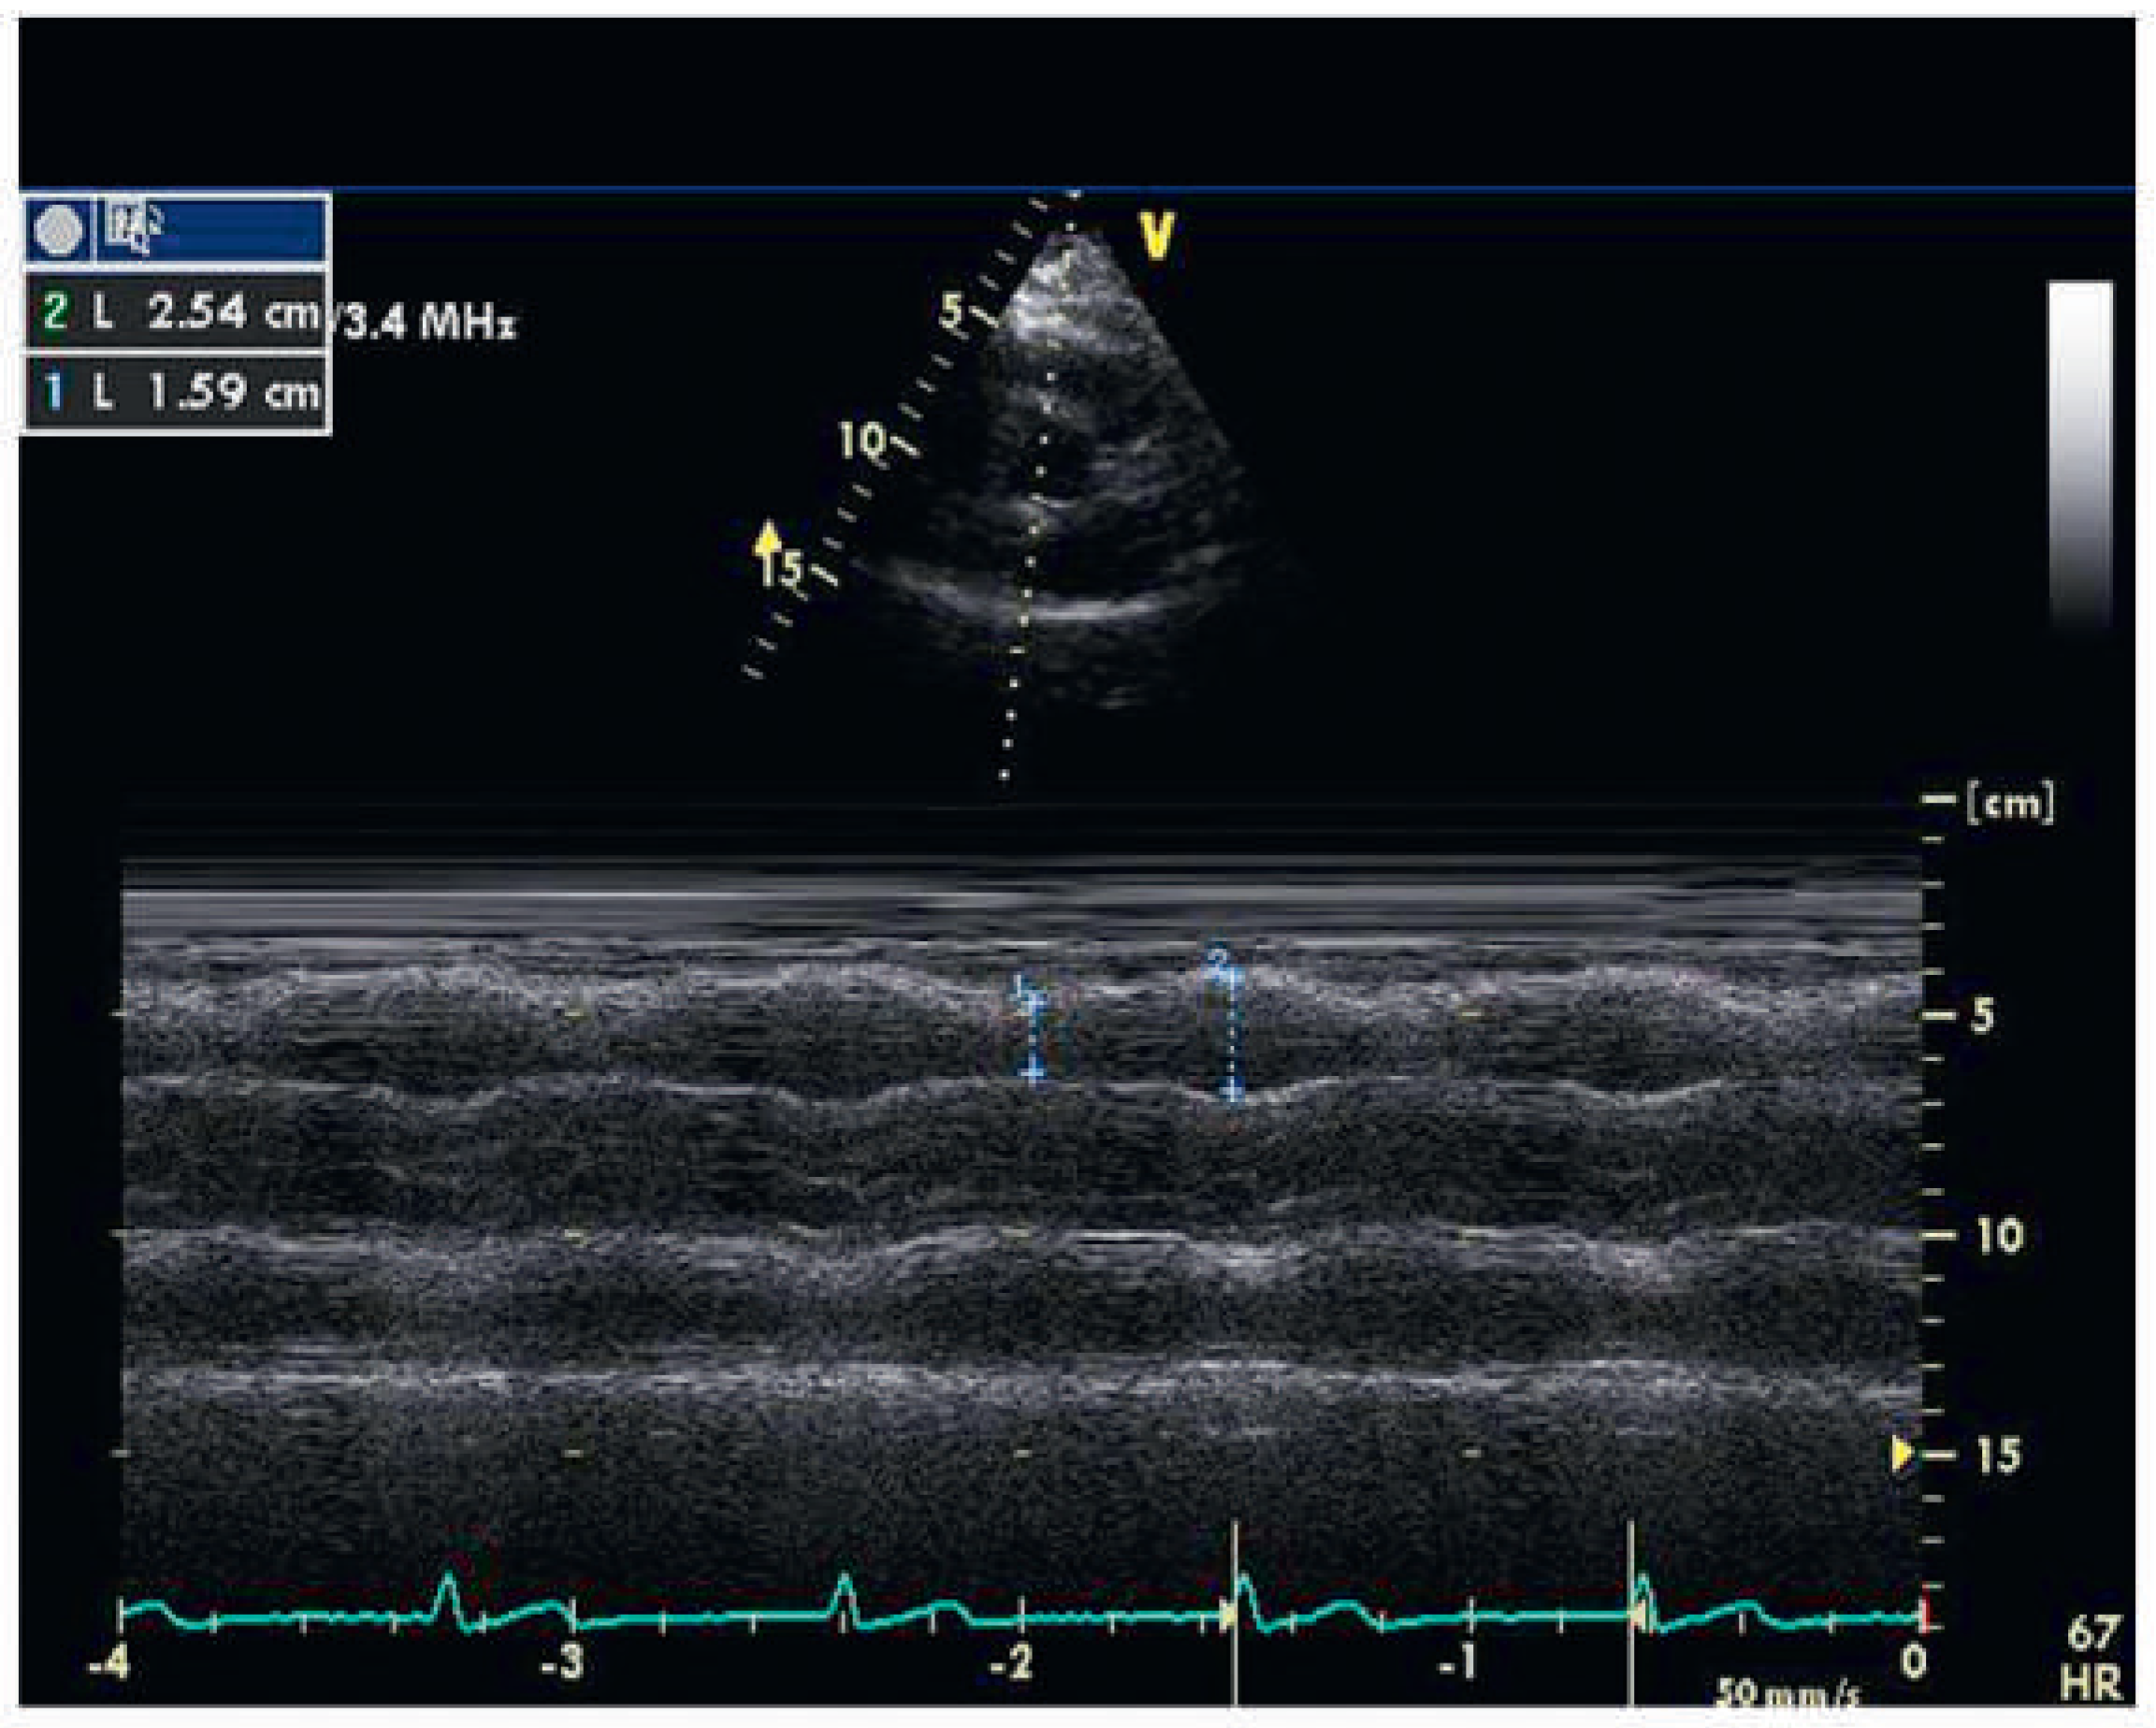

Assessment of the right ventricular function in M-mode (tricuspid annular excursion, RV outflow fractional shortening)